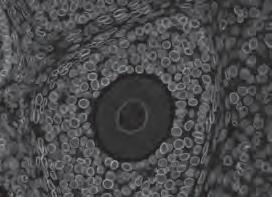

Dr Cristina Giogha studies a range of medically important bacteria that cause millions of deaths worldwide every year due to gastroenteritis, such as  E. coli, Salmonella and Shigella. It is well known that E. coli destroy intestinal structures called microvilli – tiny fingerlike projections on intestinal cells that are vital for absorbing nutrients and water from the gut – but until now there has been little understanding of the mechanics of how this occurs. 2022 brought a breakthrough, with Dr Giogha and her mentor, Professor Elizabeth Hartland, showing for the first time

the involvement of specific human and bacterial factors in the destruction of microvilli. She sums up her findings simply: “If the cell is like your home,  E. coli are like unwanted guests that remodel your home to suit themselves.”

Published in Proceedings of the National Academy of Sciences, June 2022